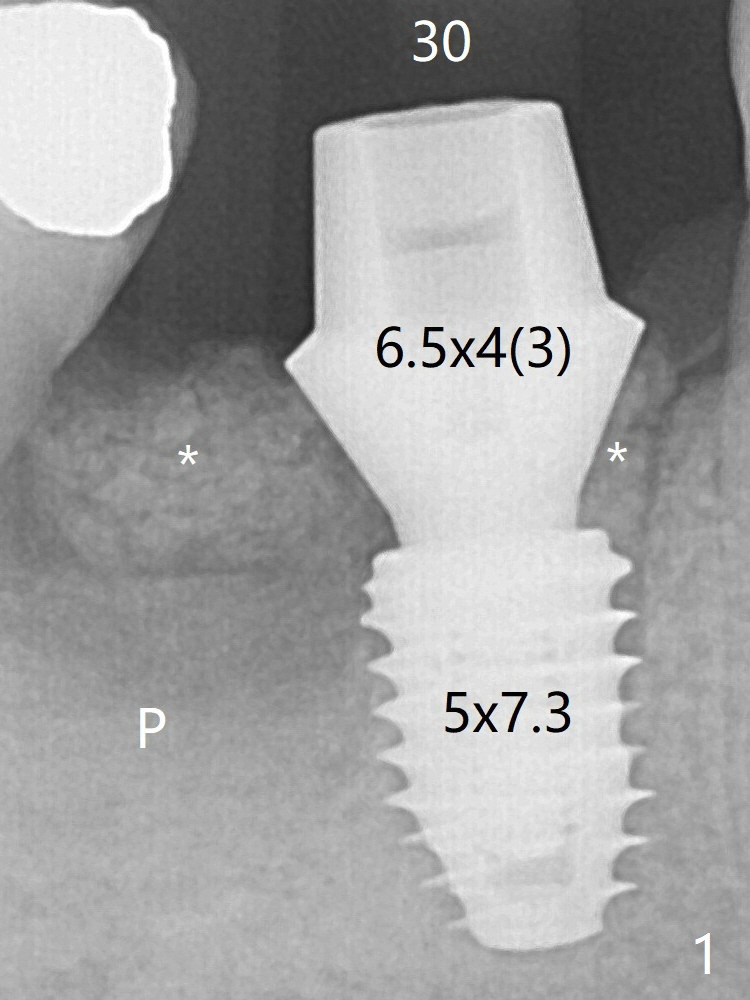

In spite of severe bone loss and 1.86 mm remaining bone after extraction of the tooth #30, a 5x7.3 mm implant achieves insertion torque of 35 Ncm with an immediate provisional (Fig.1).  Periodontal dressing is applied for additional fixation of the bone graft (*) and Osteogen plug (P).  Although the implant is placed in the mesial socket, the coronal end of the abutment is in the middle of the edentulous area.  The implant plateau seems to be covered by the bone 4.5 months postop (Fig.5).  In fact the mesiobuccal margin of the abutment is close to the corresponding crestal bone.